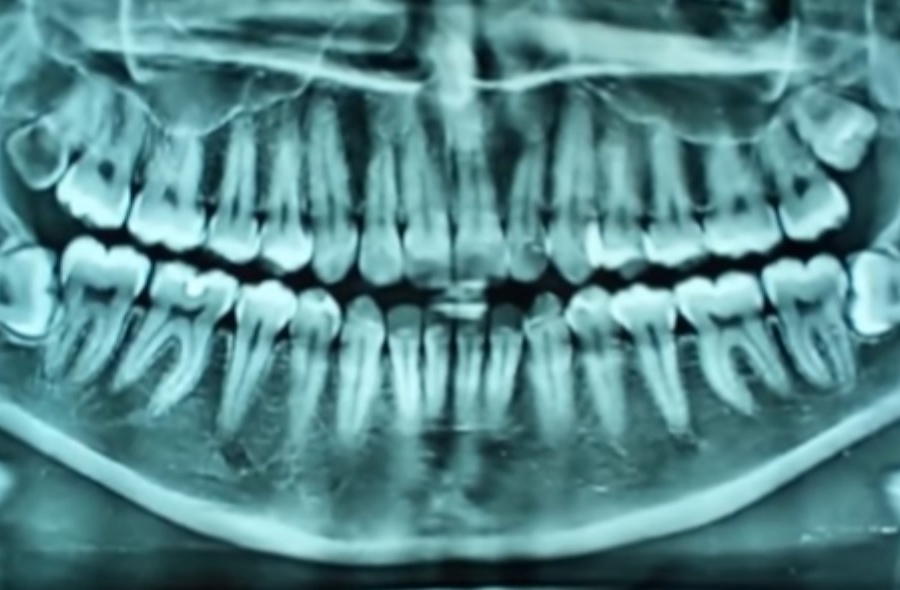

Только врач-ортодонт может судить имеются ли отклонения от норм в формировании прикуса. На основании тщательного осмотра, выполнения телеренгенограммы и ортопантомограммы доктор точно определит правильно ли формируется прикус ребенка.

Фото 3. Рентгенорамма как метод диагностирования неправильного прикуса.